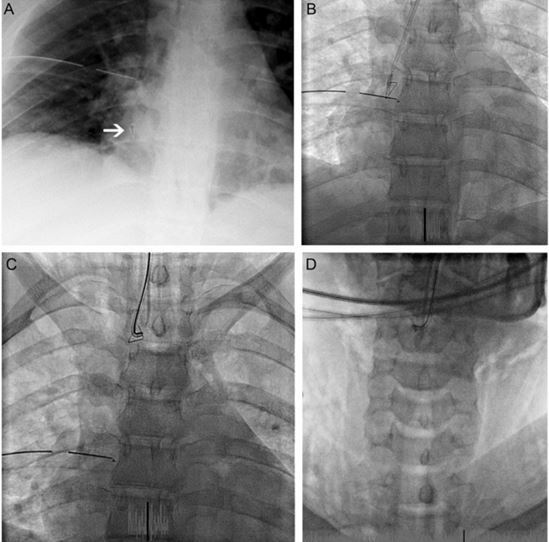

16 岁女孩因气管异物转入。入院 4 天前,患儿吸入订书钉。胸片显示订书钉位于右主支气管内(图 1 A)。起初尝试使用支气管镜取出异物没有成功,并且还造成右侧张力性气胸,进而给予胸腔闭式引流进行治疗。之后患者被转入我院。决定在心导管室内于透视介导下行异物取出,如果无效则进行外科手术。

图 1 A 胸片显示异物在右下肺叶;B 指引导管接近异物;C 用血管钳夹取异物并上升至气管;D 将支气管导管和导管一起撤回至声带以上

全麻并接机械通气后,使用 7.5 mm 的支气管导管探查支气管,使用的指引导管是 6-Fr JR-4 的,导丝为 0.035 英寸的,指引导管从支气管导管的侧孔伸出到达异物(图 1 B)。

起初尝试应用多个微型捕捞器取出异物,但是没有成功,然后使用 3-Fr 的血管钳夹取异物并送至声带水平(图 1 C)。

由于订书钉经常从血管钳上滑落,采用微型捕捞器将其固定在支气管导管的远端。之后将支气管导管、引导导管、捕捞器、订书钉一起取出,取出的过程中,订书钉的尖端朝里,以防止声带被异物损伤。透视介导的时间长度一共是 22 分钟。患者术后未出现并发症,并于第二天出院。